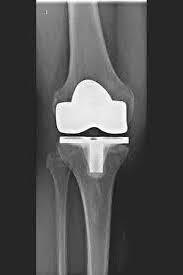

La articulación de rodilla artificial reemplaza la superficie del cartílago destruida por la osteoartritis. El hueso subyacente del fémur y la cabeza tibial permanece intacto. Algunos comparan una articulación artificial moderna de rodilla con la coronación de un diente; el término exacto es el llamado rejuvenecimiento bicondilar. Entre las nuevas superficies de la parte superior e inferior de la pierna se encuentra la llamada incrustación de un plástico blanco especialmente endurecido, que en la imagen de rayos X se puede ver como la distancia entre las piezas metálicas.